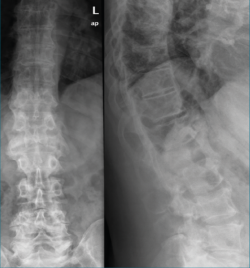

Cuando la enfermedad se confirma, el último paso es definir los focos de actividad de la enfermedad, siendo la gammagrafía(5)(Figura 4) la prueba elegida con esta finalidad; en este paciente mostró focos activos a nivel dorsolumbar, pélvico y en las costillas 7.a y 8.a.

Figura 4. Gammagrafía.